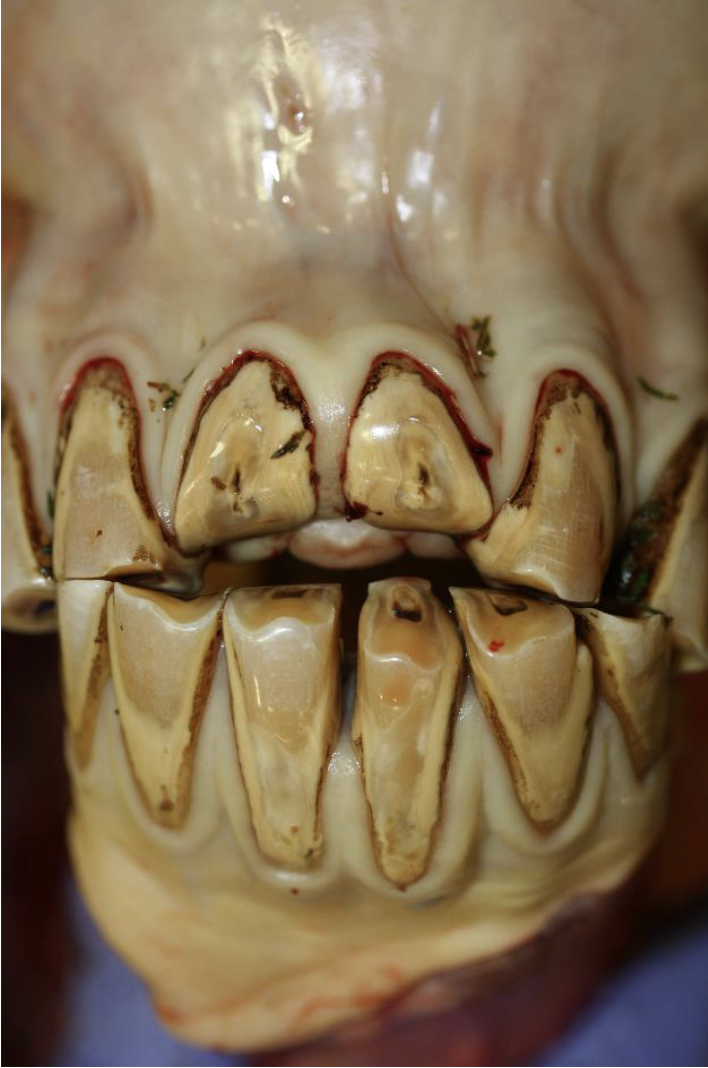

Severe dental attrition (wear and tear).